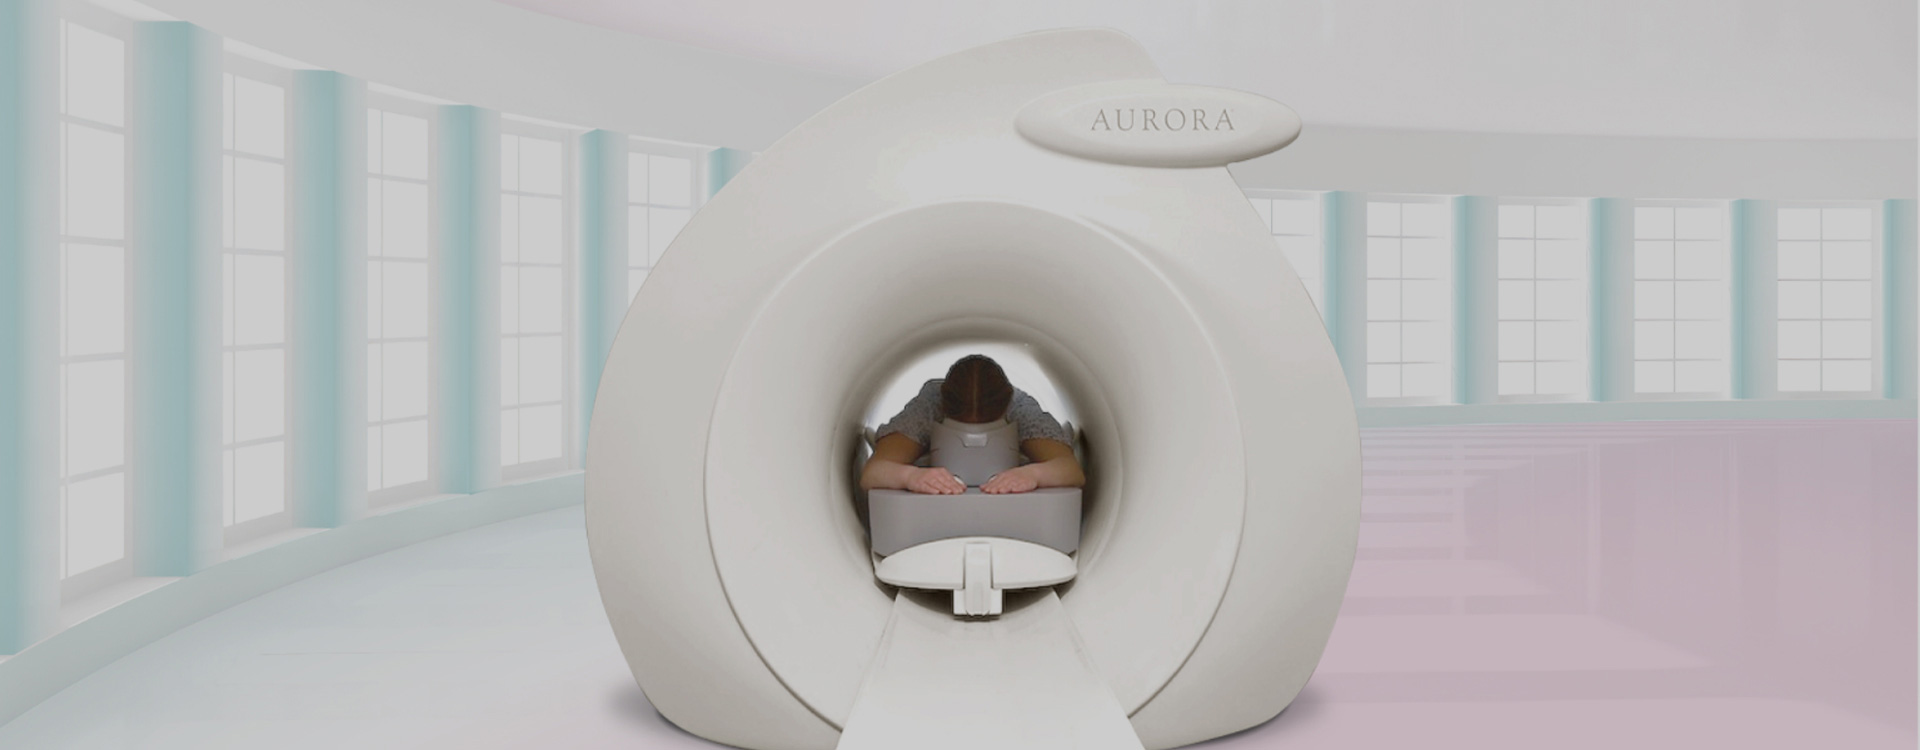

1.5T乳腺专用磁共振依托乳腺穿刺活检定位系统、计算机辅助诊断系统,可实现精准乳腺成像,为中国乃至世界女性提供专业精准的乳腺早期筛查、诊断以及全方位的体检服务。

人体工学检查床64cm大孔径开口、适合乳房解剖生理结构有效减少幽闭恐惧症、最大可承重250公斤受检者 |

独特的射频线圈适合不同乳房大小的受检者双侧乳房、胸壁和腋下淋巴组织同时完整呈现 |